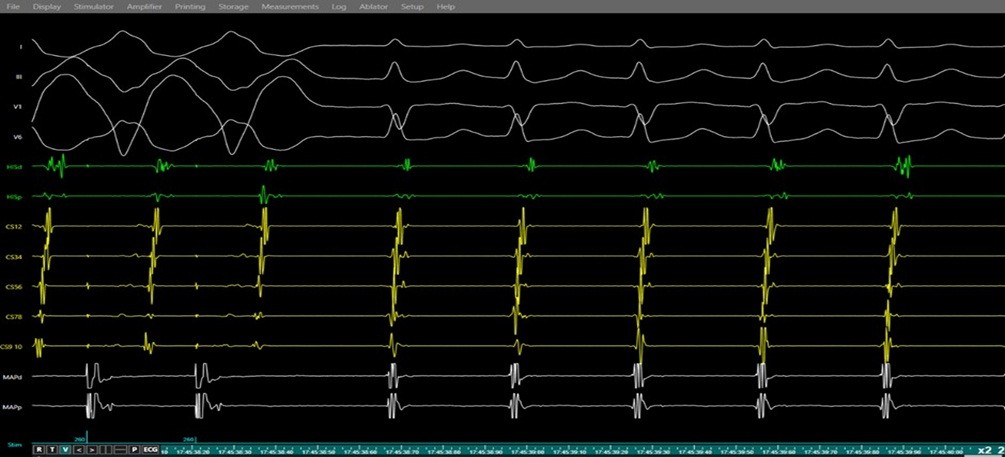

Figure 8. Entrainment response during electrophysiology study confirming AVNRT.

Simultaneous surface ECG (leads I, II, V1, V6) and intracardiac electrograms (His bundle region, coronary sinus, and right ventricular channel) demonstrating ventricular overdrive pacing during ongoing SVT. The tracings show a V–A– V response upon cessation of pacing with a long post-pacing interval–tachycardia cycle length > 115ms (PPI–TCL) difference, consistent with typical AVNRT and excluding atrioventricular reentrant tachycardia (AVRT) and atrial tachycardia.

AVNRT - atrioventricular nodal re-entrant tachycardia, ECG – electrocardiogram